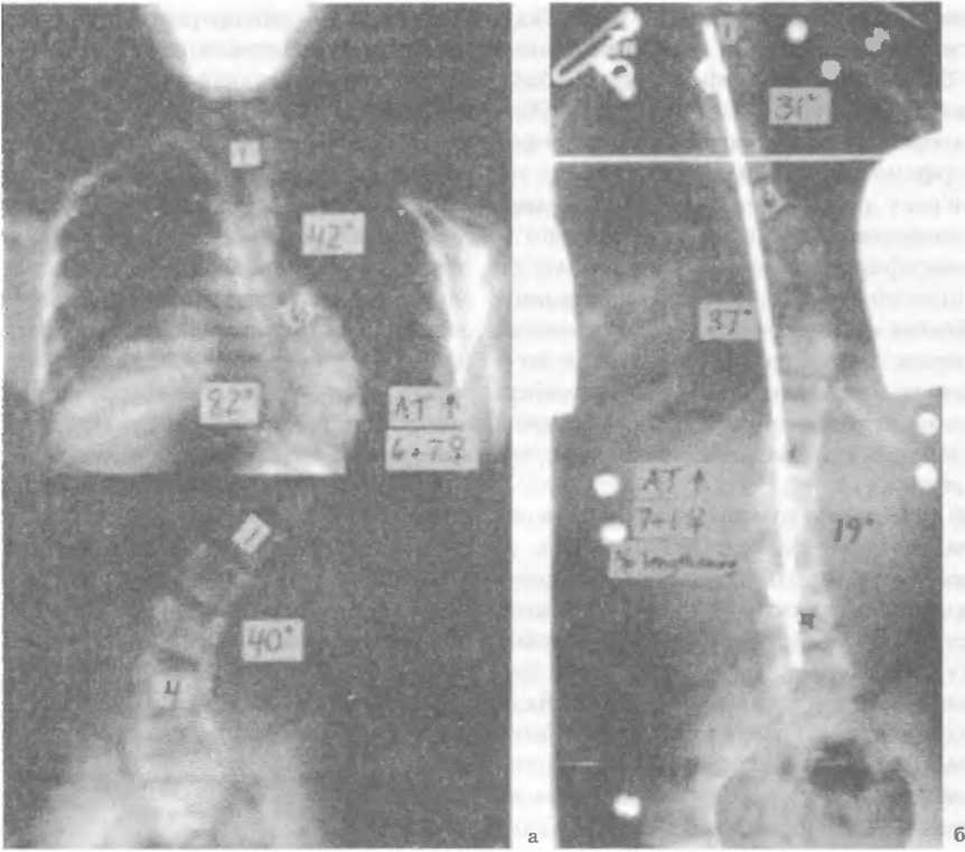

Рентгенологічні зміни залежать від віку хворого, тобто від стадії перебігу хвороби. Міжхребцеві щілини звужені і звапнілі, інколи захоплюють увесь диск або його частину у вигляді овалу звапніння діаметром у декілька міліметрів. Наявність таких тіней між багатьма хребцями характерна для охронозу хребта (мал. 70). Інколи можна виявити дрібні дефекти хребців і кісткові нашарування по краях — остеофіти. Звапніння знаходять у симфізі, хрящах ребер тощо.

Мал. 70. Деформація хребта (Сколіоз) при синдромі Марфана: а - перед операцією, б - після операції корекції на 37' і фіксації хребта від Тh2 до L5 (Hamill Ch.L., 1993).